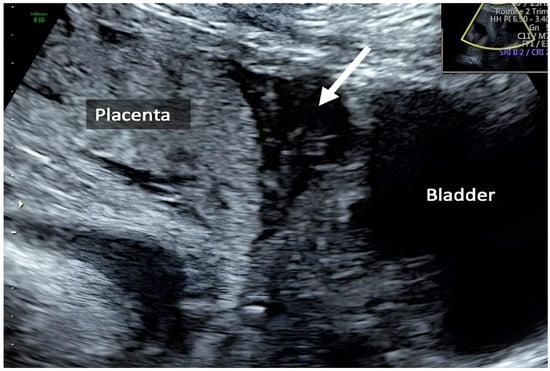

| Zermano S. et al. | 2024 | Yes | Yes | Yes | 24 5/7 | ||

| Zermano S. et al. | 2024 | 29 1/7 | No | Yes | Yes | Yes | |